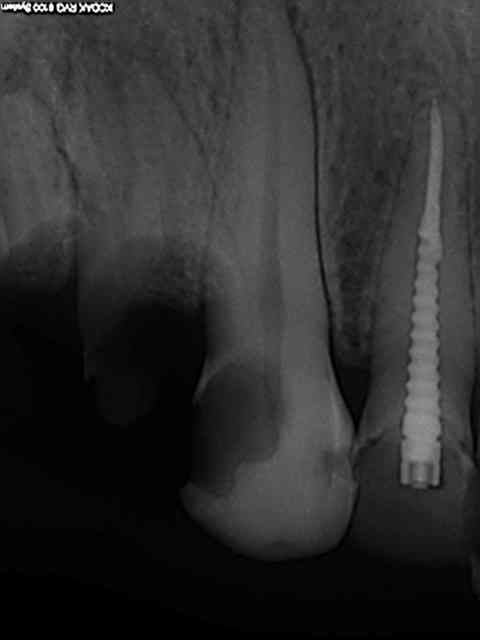

Comme celle là par exemple ? 20 ans et presque toutes ses dents )))) Mieux vaut avoir les radios initiales par les temps qui courent !